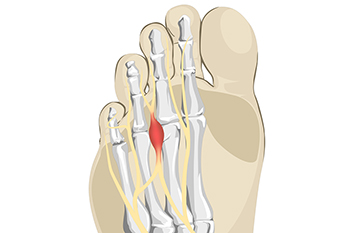

Morton's Neuroma, also called Intermetatarsal Neuroma or Plantar Neuroma, is a condition that affects the nerves of the feet, usually the area between the third and fourth toe. Neuroma refers to a benign growth that can occur in different parts of the body. Morton's Neuroma strictly affects the feet. This condition causes the tissue around the nerves that lead to the toes becoming thick, causing pain in the ball of the foot.

This condition can be caused by injury, pressure or irritation. Normally no lump will be felt, but instead burning pain in the ball of the foot will be experienced. Numbness and tingling may also occur. With the onset of this condition, a person may feel pain when tight or narrow shoes are worn. As the condition worsens, the pain may persist for days, or even weeks.

Irritated Nerve Between the Toes

Nerve tissue that forms in a specific part of the foot may indicate Morton’s neuroma has developed. This is a condition that affects the area between the third and fourth toes, and despite how painful it can be, it is generally a benign growth. It happens when this area becomes irritated or compressed, and a common cause can be from wearing shoes that do not have enough room for the toes to move freely in. High heels fit into this category, and this may be a reason why women are more affected by Morton’s neuroma than men. The discomfort that is felt from this condition is in the ball of the foot. Many patients report the pain is likened to having a small pebble in their shoe or sock and often look to feel better. There are specific stretches that can be performed which may help to find moderate relief, in addition to having regular foot massages done. If you have pain in this part of your foot, it is suggested that you consult with a podiatrist who can diagnose Morton’s neuroma, and offer you correct treatment solutions.

Morton's neuroma is a painful foot condition that commonly affects the areas between the second and third or third and fourth toe, although other areas of the foot are also susceptible. Morton’s neuroma is caused by an inflamed nerve in the foot that is being squeezed and aggravated by surrounding bones.